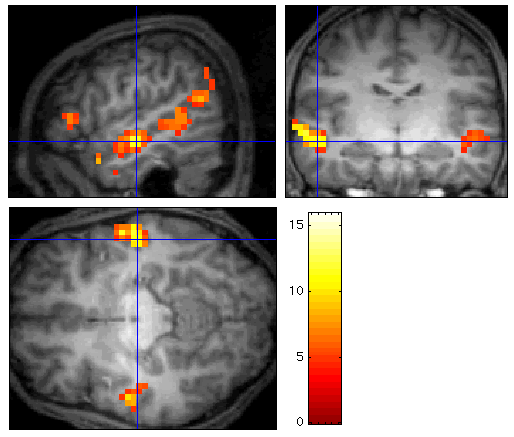

Chez aucun des adoptés, les phrases coréennes n'ont provoqué des activations cérébrales supplémentaires par rapport aux phrases polonaises ou japonaises: les stimuli de ces trois langues activaient bilatéralement les gyri temporaux supérieurs (voir figure 1). Dans la limite de l'instrument de mesure qu'est l'IRMf, on n'a donc décelé aucune trace de l'exposition précoce au coréen. De plus, les aires cérébrales mises en jeu spécifiquement par l'écoute du français (figure 2) étaient les mêmes chez les adoptés que chez les français natifs.

Figure 2: Aires plus activées lors de l'écoute de phrases en français

que par l'écoute d'une langue étrangère inconnue chez un locuteur

ayant le français comme langue maternelle.